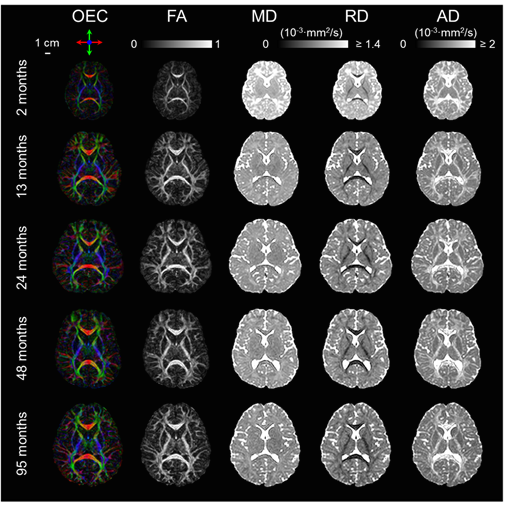

以往研究由于缺乏足够多的被试覆盖从出生到儿童早期这个关键的发育时间段,使得研究发现的发育规律深受选取的时间段和被试数量不足影响。本研究收集了118位0到8岁典型发育儿童的DTI数据,在被试数量与覆盖关键发育阶段方面均弥补以往研究不足。图2列举了从出生2个月到出生95个月儿童大脑的DTI指标图像的变化。在这个时期大脑容量增大,白质FA增大,白质MD和RD下降。

图2,纤维朝向编码颜色图(OEC)与FA,MD,RD和AD从2月到95月的发育变化过程。